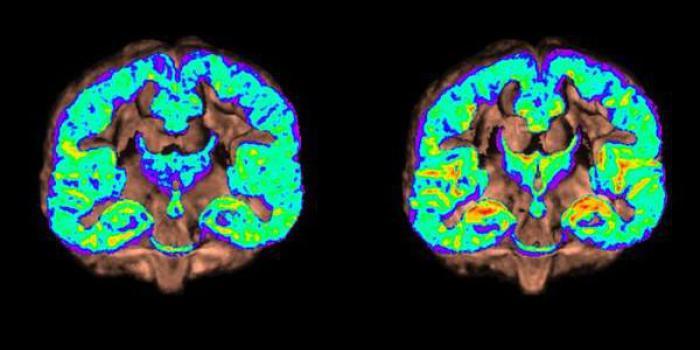

Des chercheurs britanniques ont mis au point une carte numérique "type" du cerveau afin de repérer les premiers signes d’Alzheimer, grâce aux IRM de patients. Saurez-vous reconnaître lequel est touché par la maladie ?

Cerveau droit : la disparition du lobe temporal médial signe d'Alzheimer

Les chercheurs ont ainsi noté un changement observable au niveau du cerveau, mais qui peut être difficile à repérer. Il s'agit du retrait d’une zone cérébrale appelée "lobe temporal médial" (cerveau droit sur l'image). Celui-ci contient notamment l’hippocampe et le cortex entorhinal qui contrôlent l’apprentissage et la mémoire. "Nous sommes ravis du résultat et que cette carte numérique puisse faciliter le diagnostic de maladies de démence comme celle d’Alzheimer" explique le Dr David Alexander Dickie. Le scientifique rappelle l’enjeu d’un diagnostic précoce pour une meilleure prise en charge médicale de la maladie. Son équipe souhaite maintenant collecter davantage d’IRM pour préciser leur carte et espère son utilisation d'ici 5 ans.